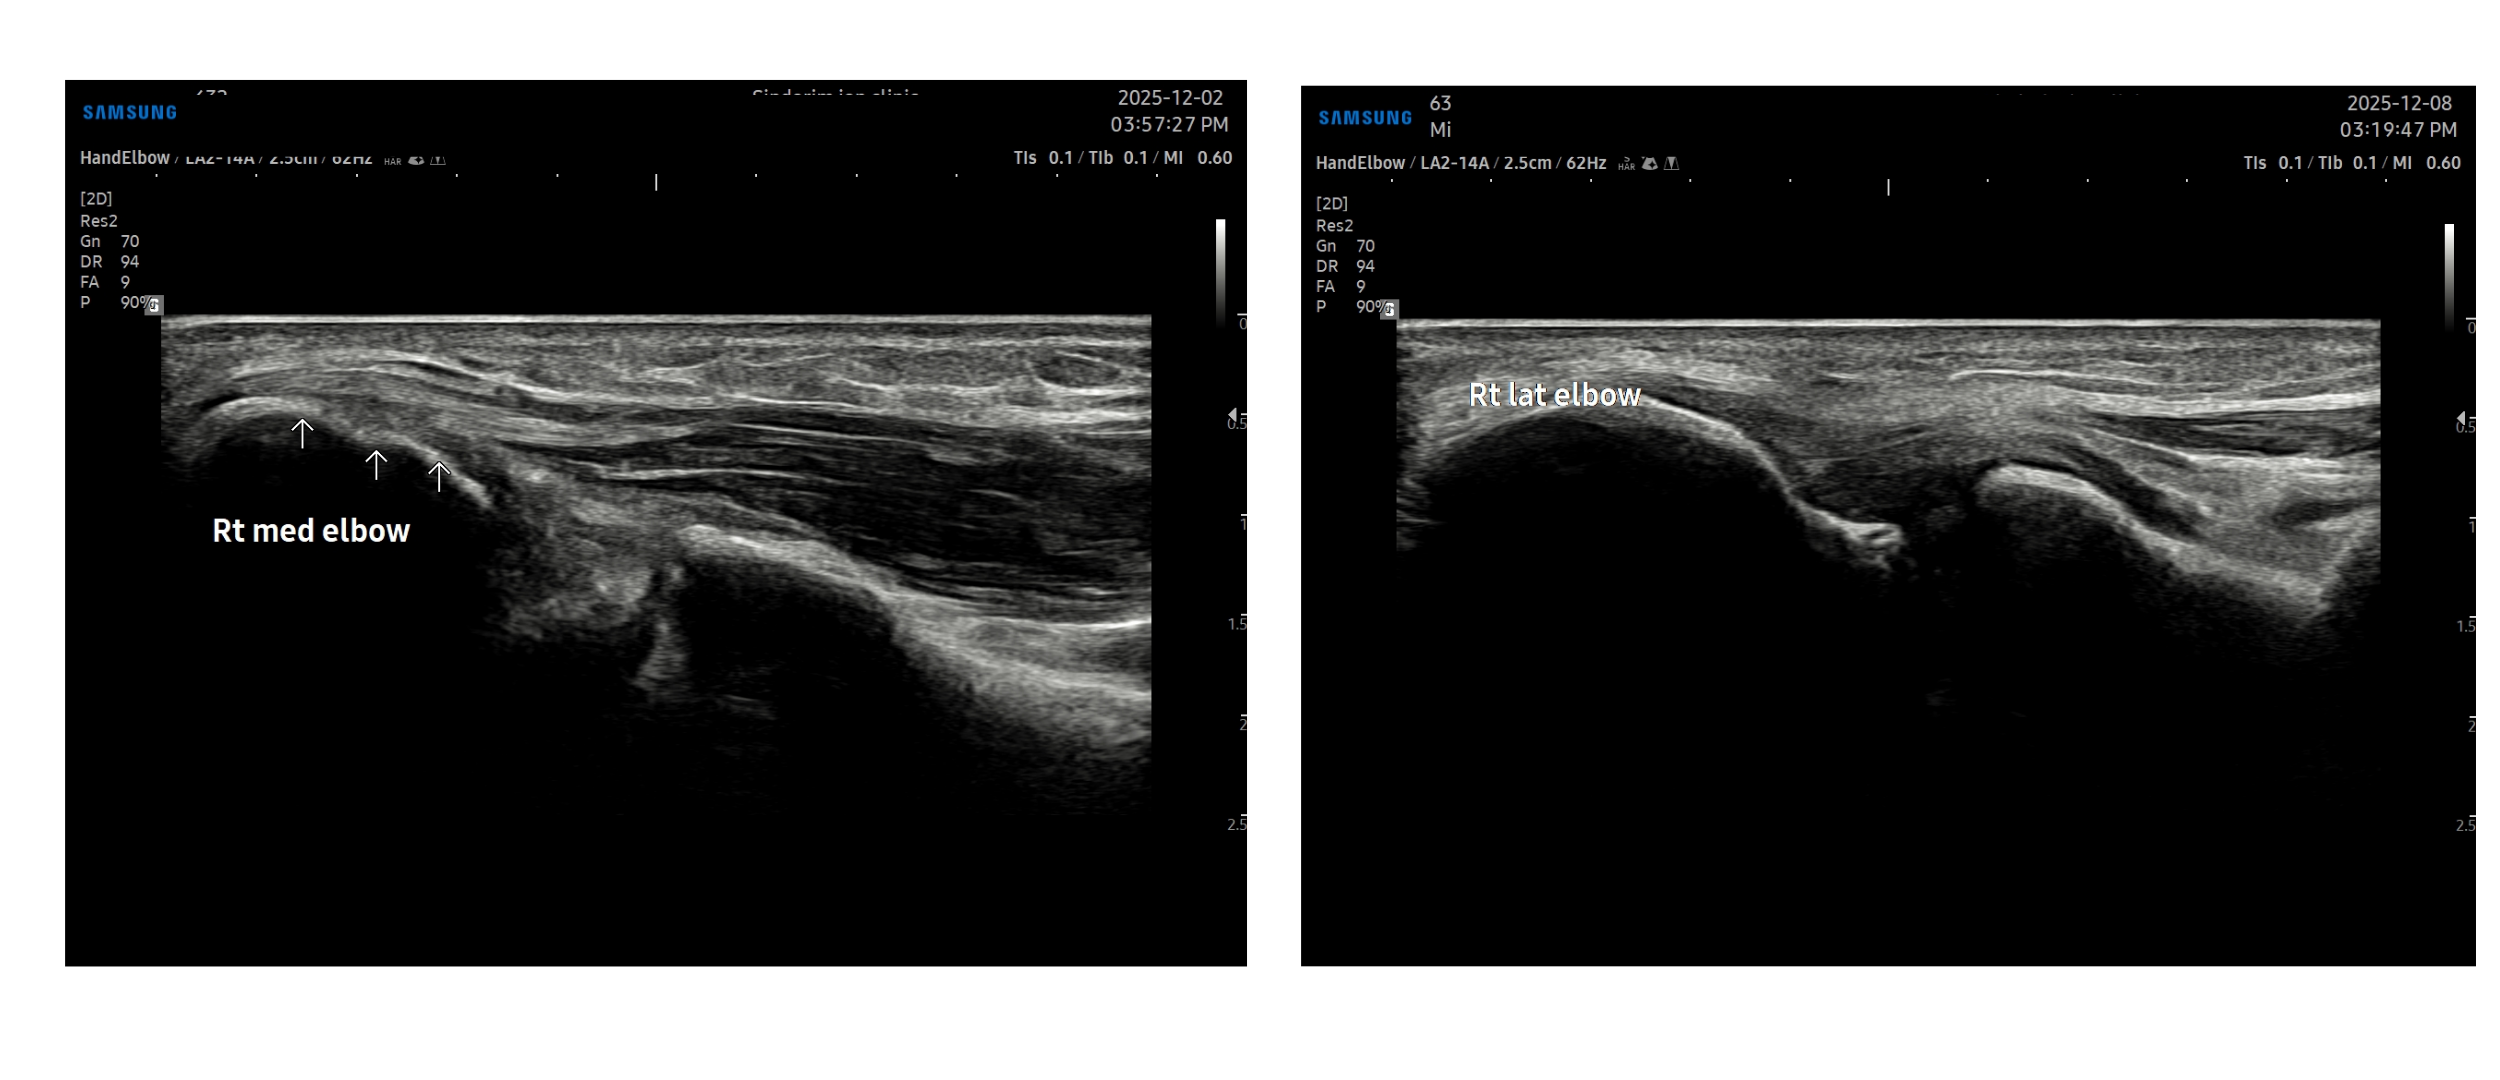

- 치료기간 : 25 . 8 .19 ~ 25 . 11 . 20

- 치료횟수 : 25 회 (사이클 치료 3 +아피톡신 10회)

치료 전

치료 후

좌측 골프엘보 : 12/2

좌측테니스엘보: 12/8

우측 골프엘보 : 12/2

우측 테니스엘보: 12/8